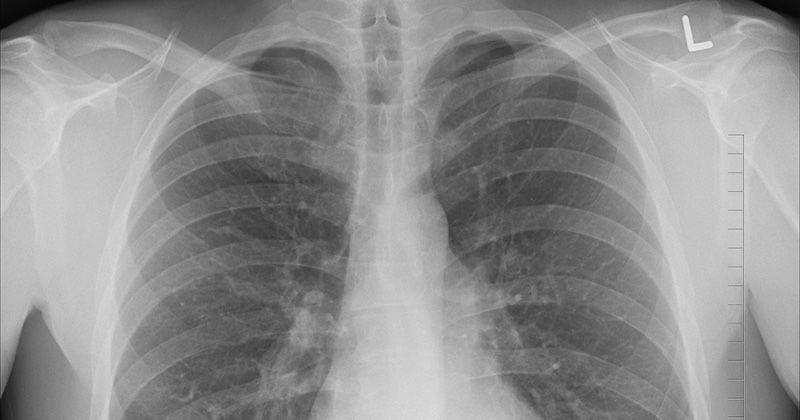

Apakah paru-paru basah itu Ma? Paru-paru basah atau yang dikenal dengan istilah kedokteran pneumonia, adalah suatu infeksi yang terjadi pada paru-paru. Setiap orang memiliki dua paru-paru. Infeksi bisa terjadi pada salah satu atau keduanya.

Pneumonia bisa terjadi hanya di salah satu bagian paru saja, paru-paru kiri atau kanan, atau bahkan keduanya. Infeksi atau peradangan yang melanda paru-paru akan membuat kantung udara alveoli ini terisi cairan.

Sejatinya, hal itu disebabkan oleh reaksi tubuh yang melawan kuman, yang akhirnya meradang. Akibatnya, paru-paru pun tak dapat berfungsi dengan normal. Oksigen pun tak bisa masuk ke dalam darah dan diedarkan ke seluruh tubuh.